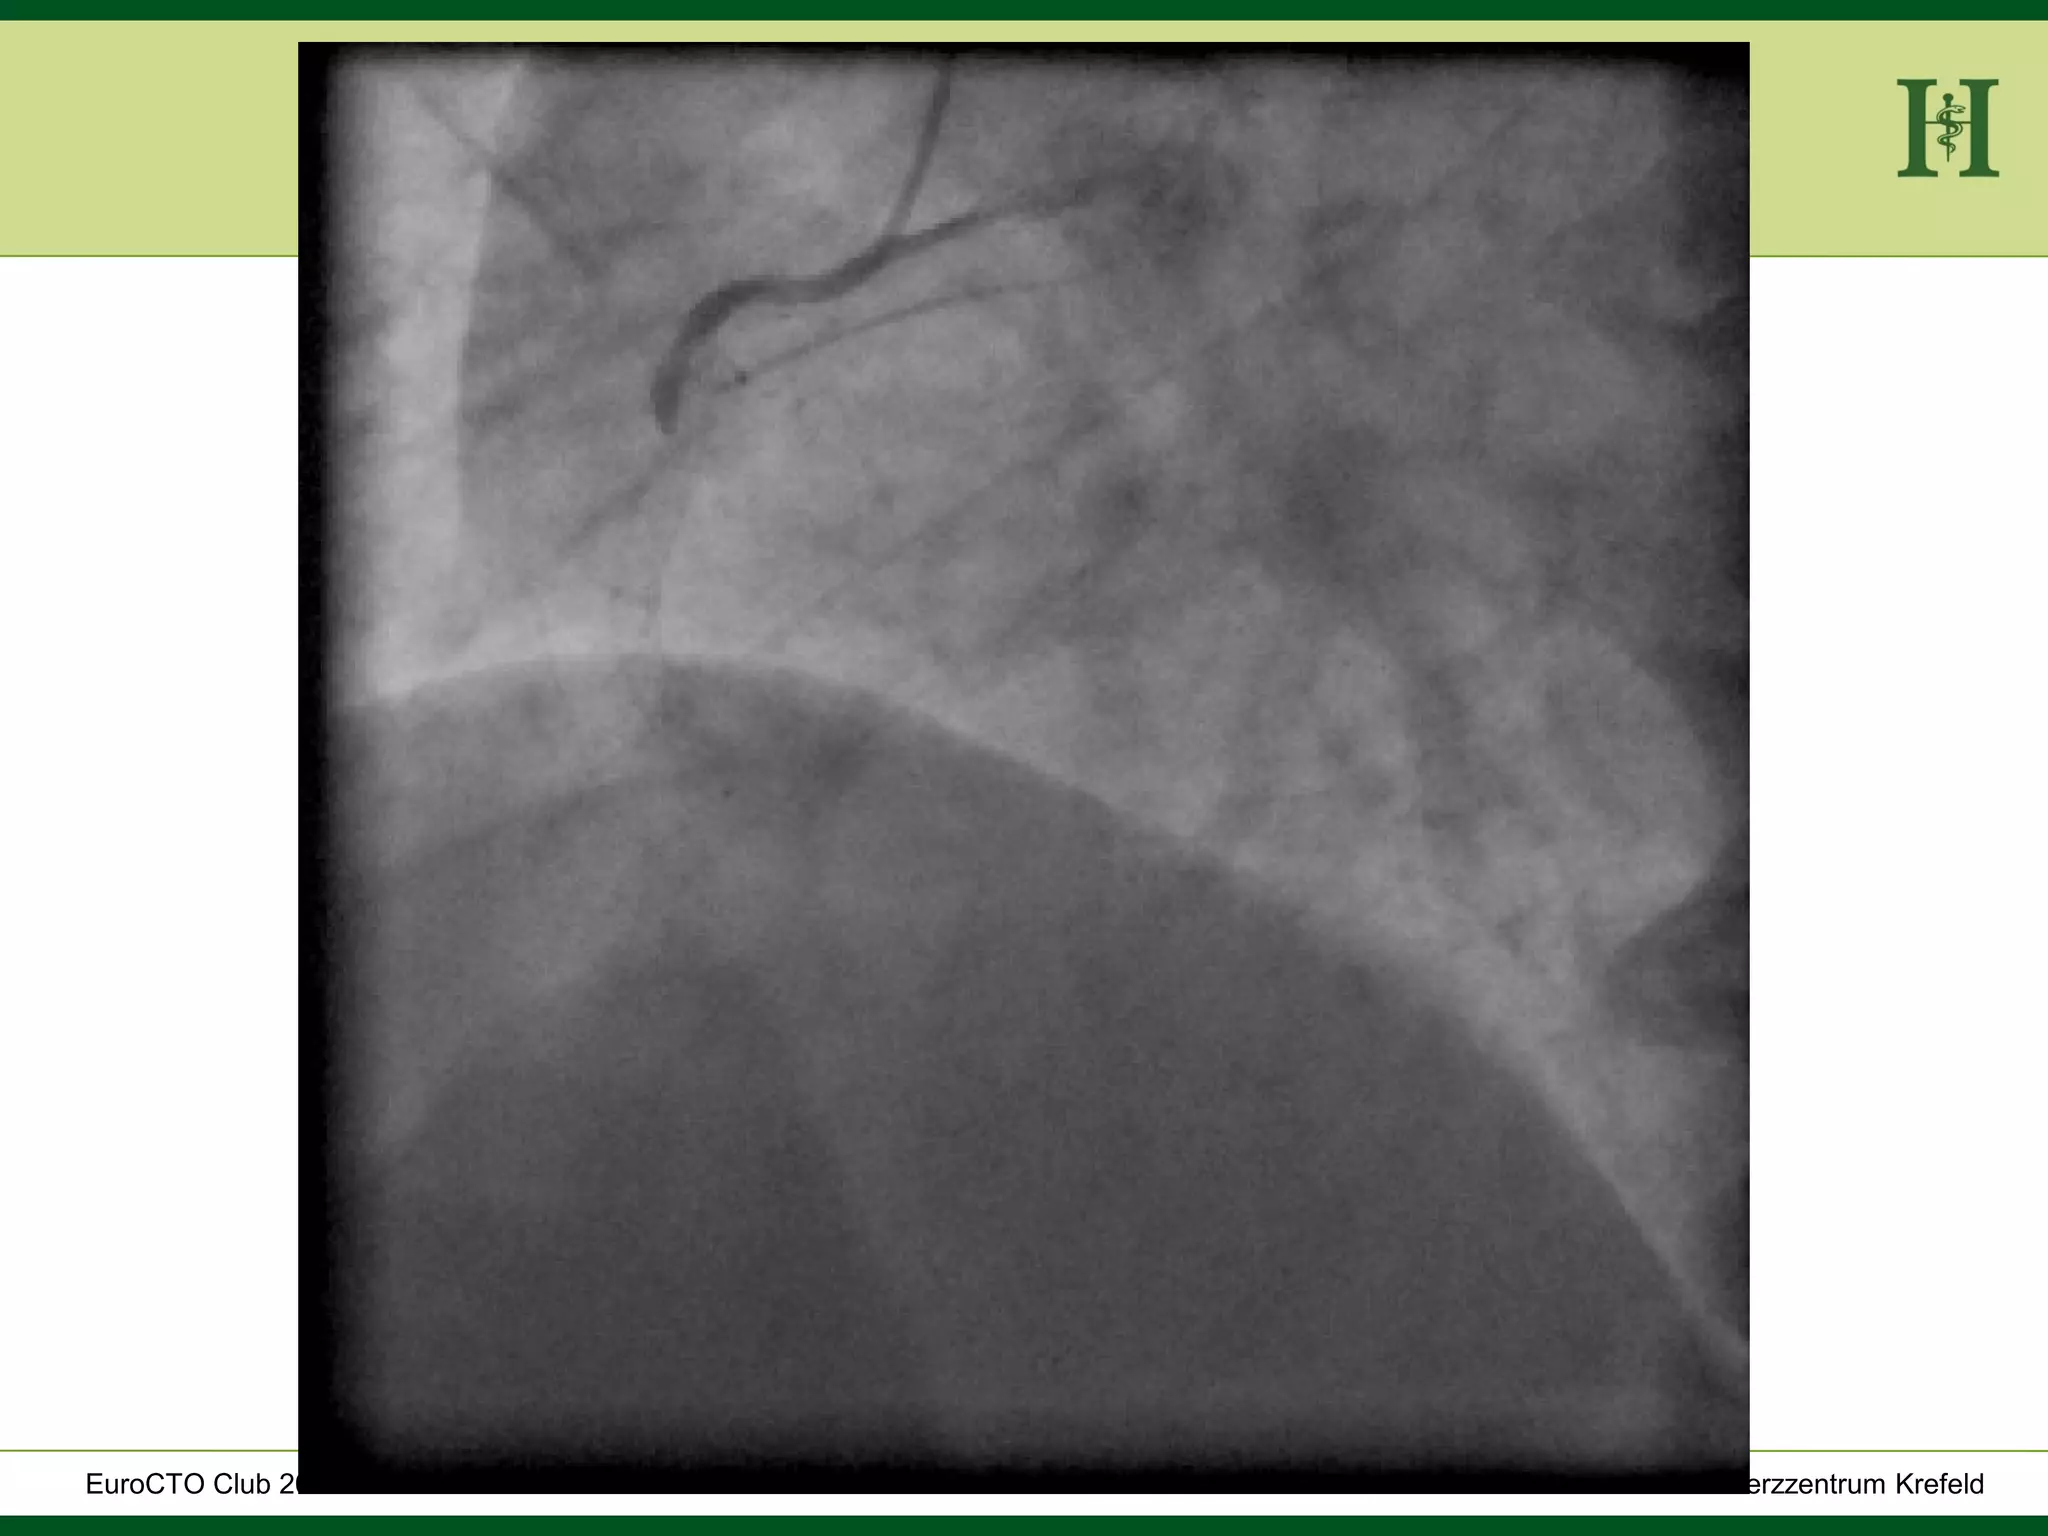

Male Patient, 55 years old

History:

 PCI 2015 with DES in LAD and in proximal RCA and

in PLD

 Angina pectoris CCS III for 7 months

 170cm, 75Kg

 RF: HLP, hypertension, smoking, HLP, familiy history

 Echo: Normal LV-Function, EF 65%

 Ischaemia inferior (MRI)